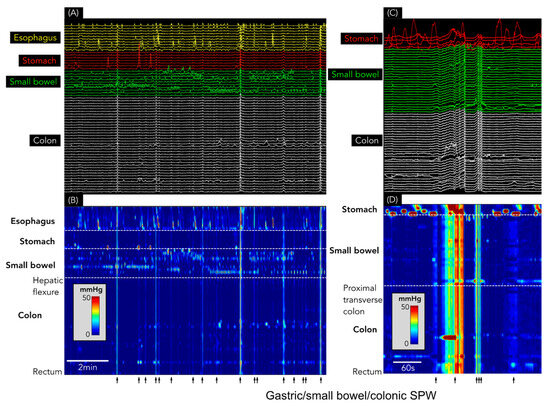

Figure 3.

(A) Conventional line plot of simultaneous pressure waves spanning the oesophagus (yellow), stomach (red), small bowel (green), and colon (white). (B) shows the same data as a spatiotemporal colour map. Note that the simultaneous pressure waves (identified by each black arrow) span the entire digestive tract from the oesophagus to the rectum. (C) Conventional line plot shows the gastric/small bowel/colonic SPW. (D) shows the same data as a spatiotemporal colour map. In these examples, the SPW can be seen to consist of varying durations, from <5 s to >30 s.

SPWs were found in each of the 39 recordings, with 14,565 identified in total (364 ± 316 SPWs/study; range: 5–1278). Of these, 14,550 (99.9%) spanned the entire antroduodenal (and, in some, oesophagal) and colonic recording sites and were, therefore, labelled as gastric/small bowel/colonic SPWs (Figure 3). Only 15 colonic only SPWs (0.1% of the total) were identified, all occurring in a single patient with constipation over an 80 min period (Figure 4).

In two other publications by Chen et al. [2,3], the pressure-wave duration of SPWs included a much broader range (2–57 s). The majority of SPWs recorded in the current study resembled SPWs in those studies (see Figure 6 in [3] and Figure 10 in [2]). An analysis of our data showed that 100% of SPWs with a duration of <10 s or >35 s spanned the entire digestive tract, from the stomach (or oesophagus) to the rectum. Given the extent of the regions involved and the differing neural innervation of those regions, it seems highly unlikely that these simultaneous pressure waves represent a highly coordinated pan-gut contraction.